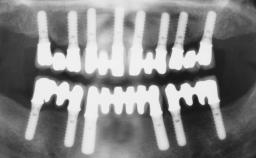

Transition from an “irrational to treat” Maxillary Dentition to a Full-Arch Segmented FDP by Early Loading of Eight Implants Placed Using the Staged Approach

The staged approach permits the transition from an “irrational to treat”dentition to a full arch implant supported restoration without any need to use a removable provisional prosthesis or to apply the immediate-placement and immediate-loading techniques.  A failing dentition is the usual indication for a staged treatment. On the other hand, the dentition should still contain many residual teeth, but with few or none of them being suitable for use as definitive abutments for a full-arch fixed restoration.This situation is usually the result of advanced periodontal disease or of the failure of an extensive fixed prosthesis.

Prosthesis Type FDP

SAC Level Complex

Defining Characteristics Fully edentulous upper jaw to be rehabilitated with an implant-borne fixed dental prosthesis

Loading Protocol Conventional or early